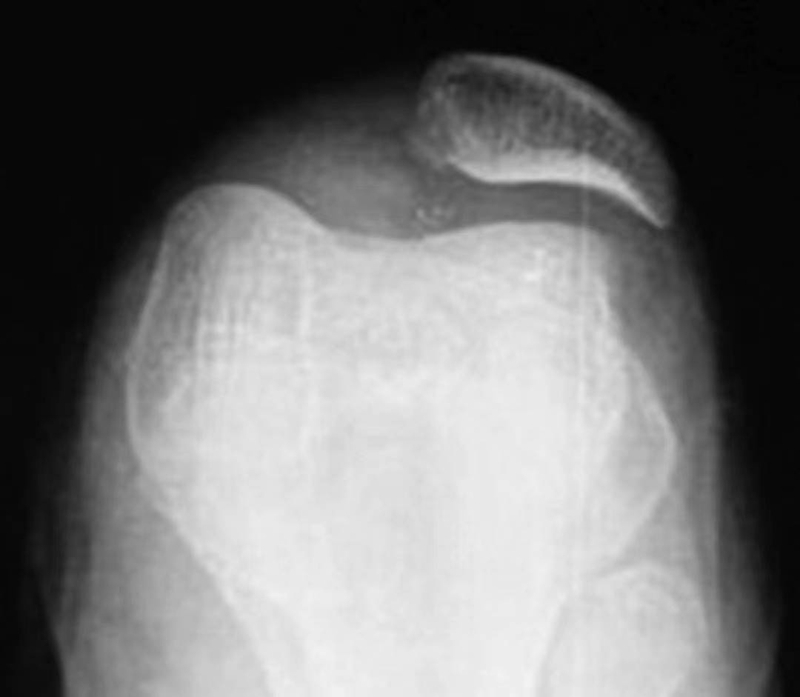

WibergⅢ型(图12):髌骨内侧关节面非常短小,而且内侧关节面的方向与外侧关节面几乎垂直,髌骨嵴位于内侧,又称猎人帽状,约占25%。易发生软骨软化和髌股关节病。

图12 WibergⅢ型髌骨轴位X线片

对于复发性髌骨脱位,髌骨的形态多为WibergⅡ型;如果患者为严重的滑车发育不良,髌骨表现为WibergⅢ型。